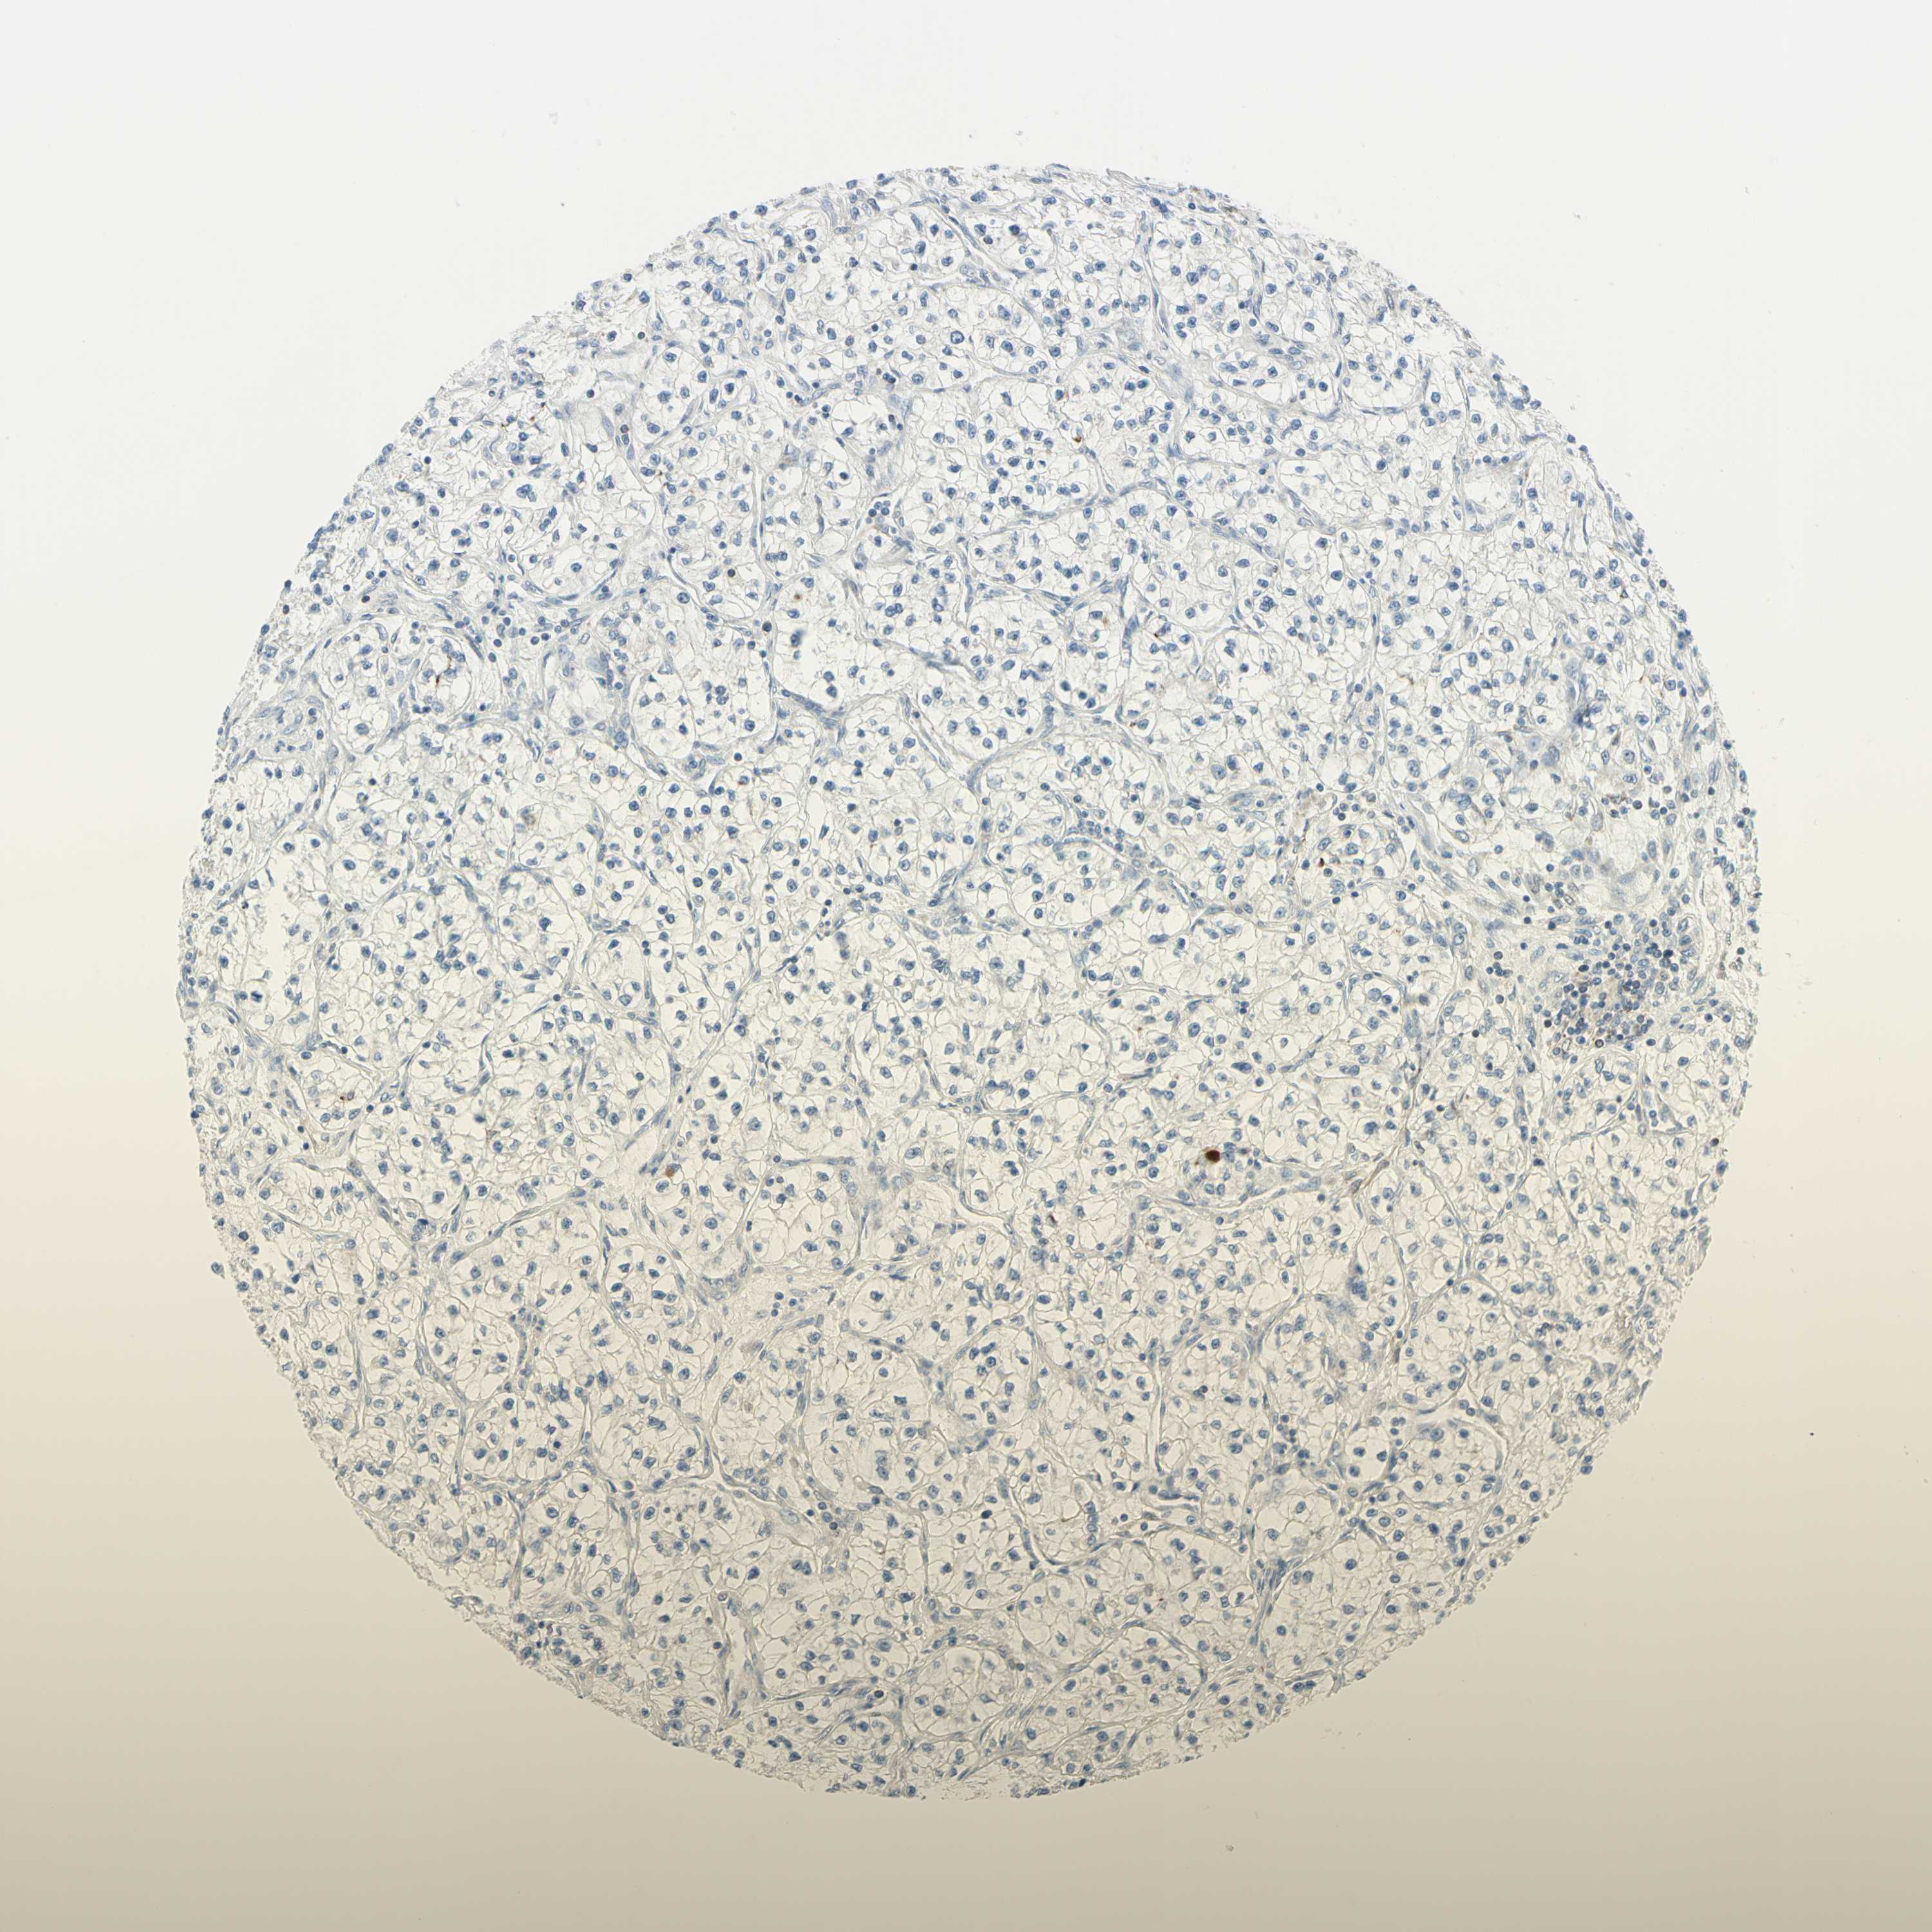

CANCER RENAL CANCER Show tissue menu

KICH TCGA KIRC TCGA KIRC VALIDATION KIRP TCGA PROTEIN RCC CPTAC PROTEIN EXPRESSION

Kidney renal clear cell carcinoma